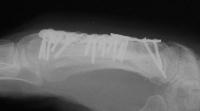

The plate was removed, and the fracture was replated, using more bone graft and larger screws. This plate  held for five months, then also broke. Additionally, a cross union to the ring metacarpal can be seen:

Click for larger image